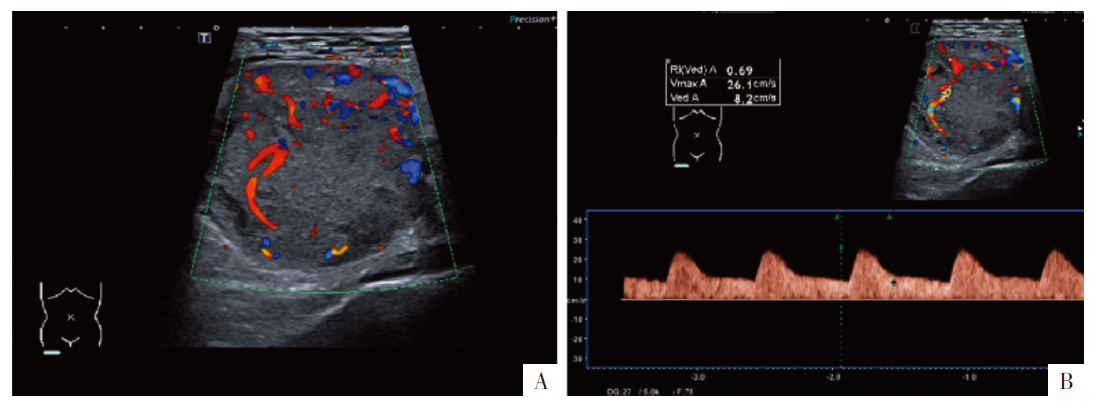

图1

病人女,23岁,下肢软组织恶性PEComa,伴

TFE3

重排。A图为肿块横切面彩色多普勒超声图,B图为频谱超声图。软组织内可见较均匀低回声肿块,边缘光整,血流丰富,以周边分布为主,大小约8.0 cm×7.0 cm;收缩期峰值(Vmax)为26.1 cm/s,舒张末期血流速度(Ved)为8.2 cm/s,阻力指数(RI)为0.69,呈中阻频谱。